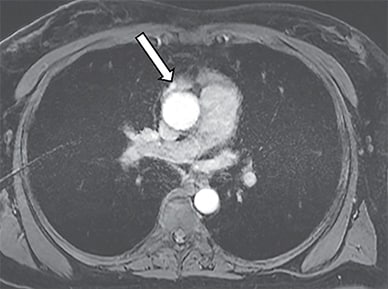

Arterial phase MRI of the chest

Arterial phase magnetic resonance imaging of the chest confirmed an enhancing 7-mm nodule (arrow) in the right lobe of the residual thymus in the anterior mediastinum.

Arterial phase magnetic resonance imaging of the chest confirmed an enhancing 7-mm nodule in the right lobe of the residual thymus in the anterior mediastinum, corresponding to the focal sestamibi uptake on SPECT imaging.